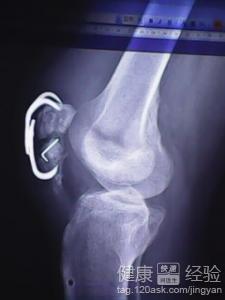

首先,得先了解一下什么是髌骨骨折。髌骨,也就是我们常说的膝盖骨,是人体最大的籽骨,位于膝盖前方。它不仅起到保护膝关节的作用,还能帮助我们在运动时更好地发力。髌骨骨折,顾名思义,就是膝盖骨发生了断裂。